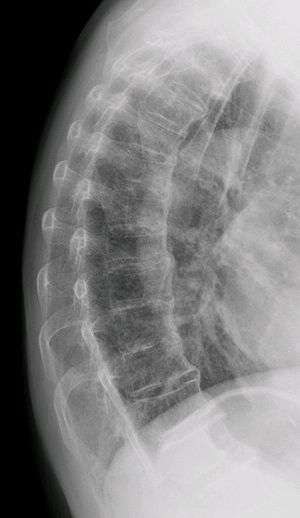

Diffuse idiopathic skeletal hyperostosis. Woman of 80 years old, also with Th11 fracture.

Diffuse idiopathic skeletal hyperostosis (DISH) is a non-inflammatory spondyloarthropathy of the spine. It is characterized by spiny ankylosis and enthesopathy (ossification of the ligaments and entheses). It most commonly affects the thoracic and thoraco-lumbar spine, but involvement is variable and can include the entire spine.[1] The disc spaces, facet and sacroiliac joints remain unaffected. Diagnosis requires confluent ossification of at least four contiguous vertebral bodies.[1] Classically, advanced disease may have "melted candle wax" appearance along the spine on radiographic studies.[2]

The exact cause is unknown. Mechanical factors, dietary and long term use of some antidepressants may be of significance. There is a correlation between these factors but not a cause or effect. The distinctive radiological feature of DISH is the continuous linear calcification along the antero-medial aspect of the thoracic spine. The disease is usually found in people in their 60s and above, and is extremely rare in people in their 40s and 30s. The disease can spread to any joint of the body, affecting the neck, shoulders, ribs, hips, pelvis, knees, ankles, and hands. The disease is not fatal, however some associated complications can lead to death. Complications include paralysis, dysphagia (the inability to swallow), and pulmonary infections. Although DISH manifests in a similar manner to ankylosing spondylitis, these two are totally separate diseases. Ankylosing spondylitis is a genetic disease with identifiable marks, and affects organs. DISH has no indication of a genetic link, and does not affect organs other than the lungs, which is only indirect due to the fusion of the rib cage.[3]